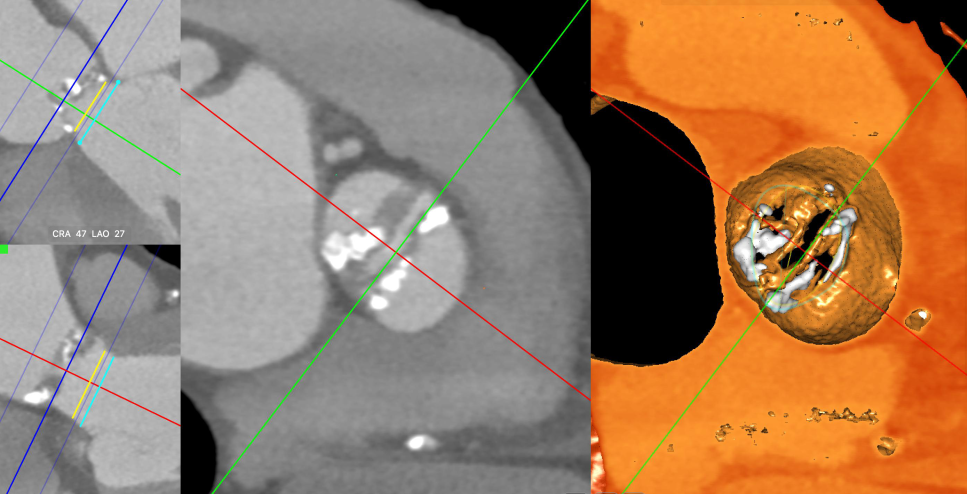

主动脉CT

主动脉瓣环周长79.6mm(平均直径25.4mm),流出道周长87mm(平均直径27.7mm),左冠高度:15.2mm,右冠高度:14mm,主动脉窦宽26.7mm/40.1mm、STJ周长:133.8mm(平均直径42.6mm)高度24.1mm,升主动脉周长:165.5mm(平均直径53mm)。

主动脉根部

入路情况

横位心角度:70度

钙化情况:3D重建

钙化积分:510